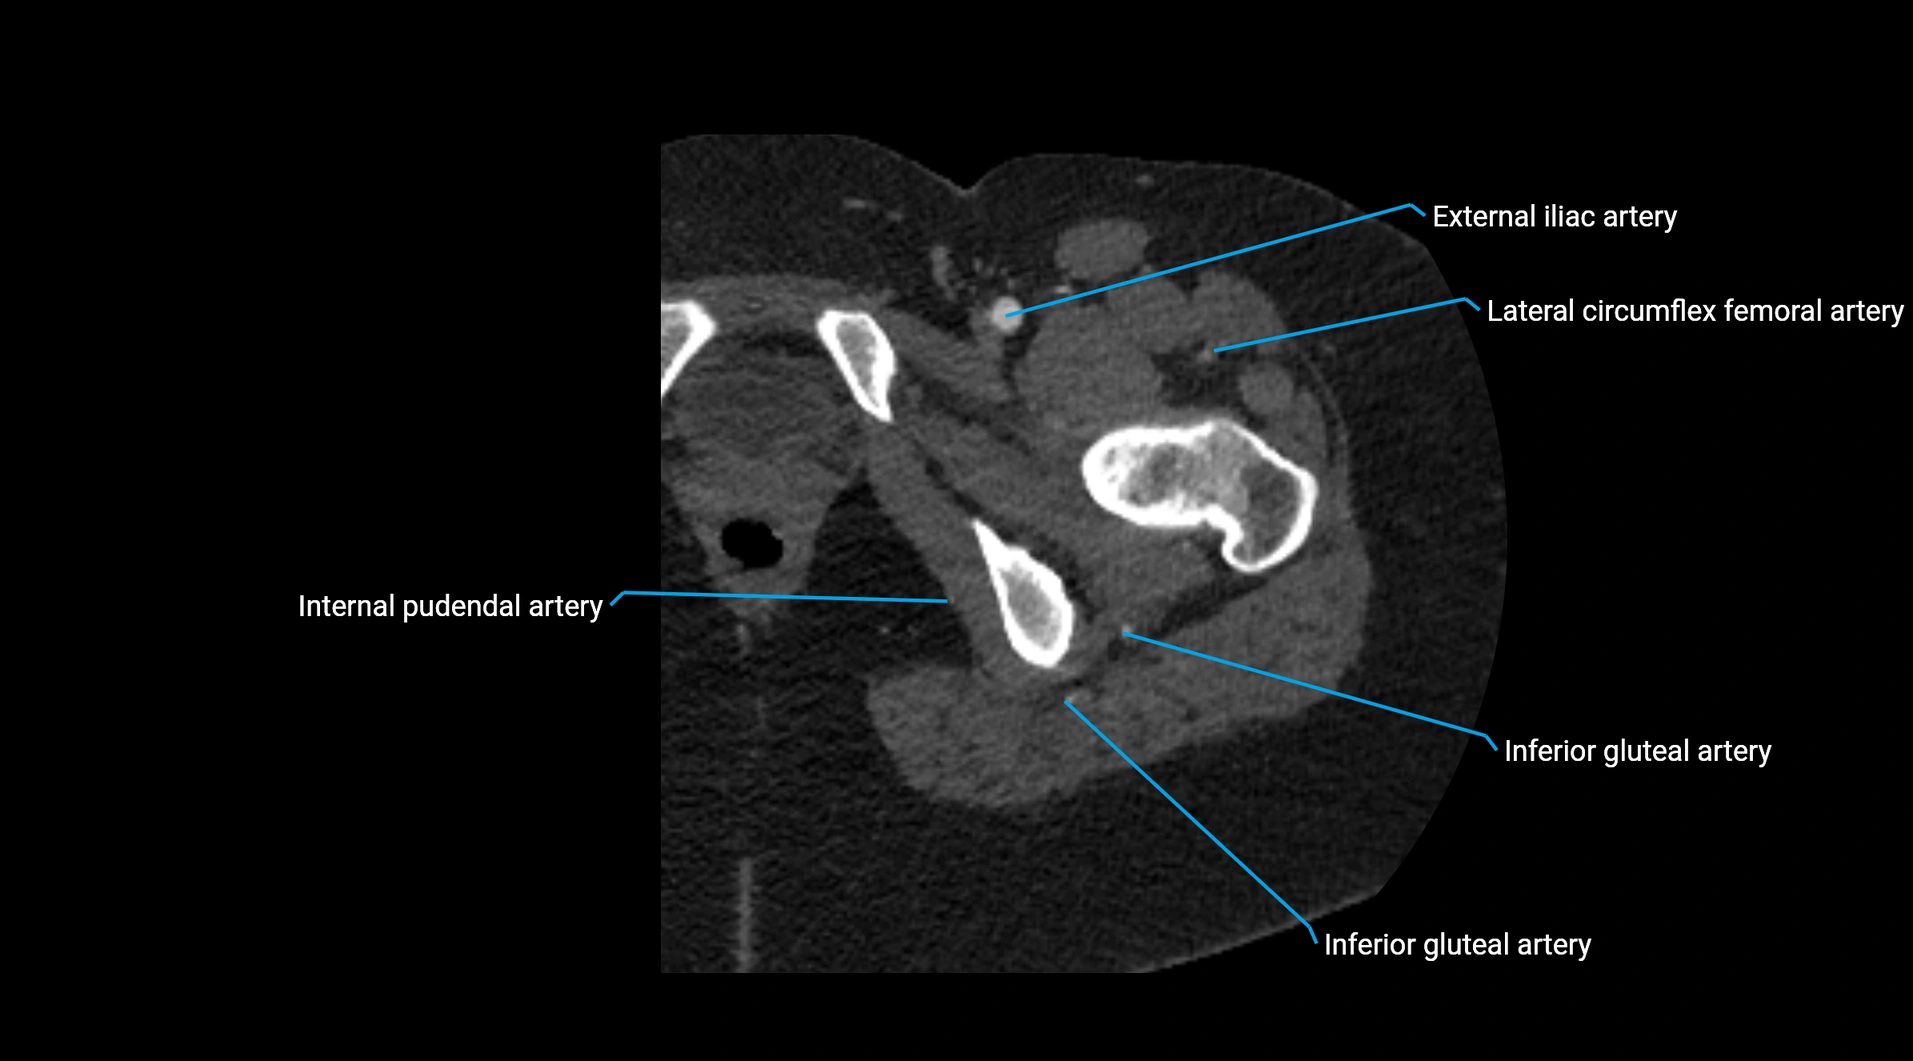

CT images

image